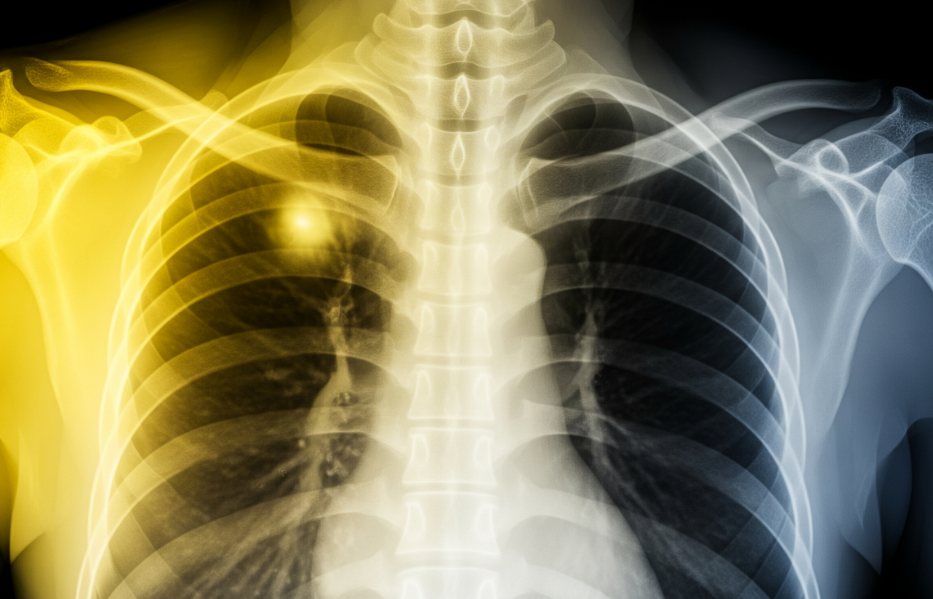

5. 폐렴 및 결핵

발열, 오한, 호흡 곤란과 기침, 가래가 있다면 폐렴일 수 있어요. 결핵은 기침 외에 미열, 식은땀, 체중 감소 등이 서서히 나타나는 감염병입니다. 전신 증상이 있다면 즉시 병원에 방문해야 합니다. 2025년에도 중요한 감염병이에요.